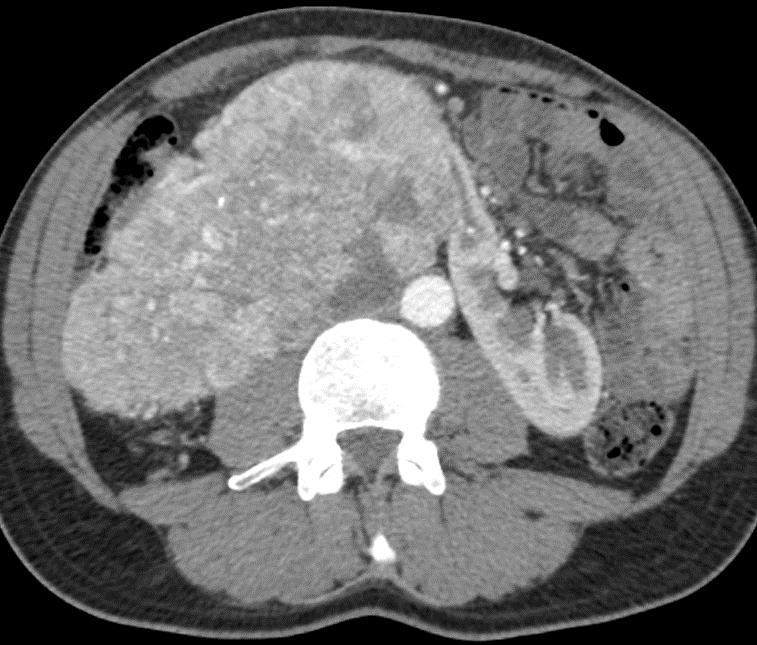

Obr. 1. Perioperační CT snímek během MWA.

Fig. 1. Perioperative CT scan during microwave ablation.

Výkon byl prováděn mikrovlnným systémem Solero Microwave Tissue Ablation System (AngioDynamics, Inc., USA). Během ablačních výkonů byla používána frekvence 2,45 GHz a výkon v rozsahu 100–140 W. Jako aplikátor byla používána nerezová ocelová jehla s keramickým hrotem o průměru 15 G a délce 14, 19 nebo 29 cm. Jedna ablační sekvence po zavedení jehly do tumoru trvá 4–6 min podle velikosti nádoru, v průběhu jednoho výkonu jsou standardně prováděny 1–2 ablační sekvence. Maximální velikost ablační zóny udávaná výrobcem je 54 × 39 mm na jednu sekvenci. Po skončení ablace tumoru se během vytahování jehly provádí ablace-koagulace punkčního kanálu (track ablace). Výkon je prováděn v analgosedaci za přítomnosti anesteziologa, pacienti snášejí výkon dobře. Celková doba výkonu vč. polohování pacienta a přípravy CT pracoviště je 60–90 min (obr. 1).